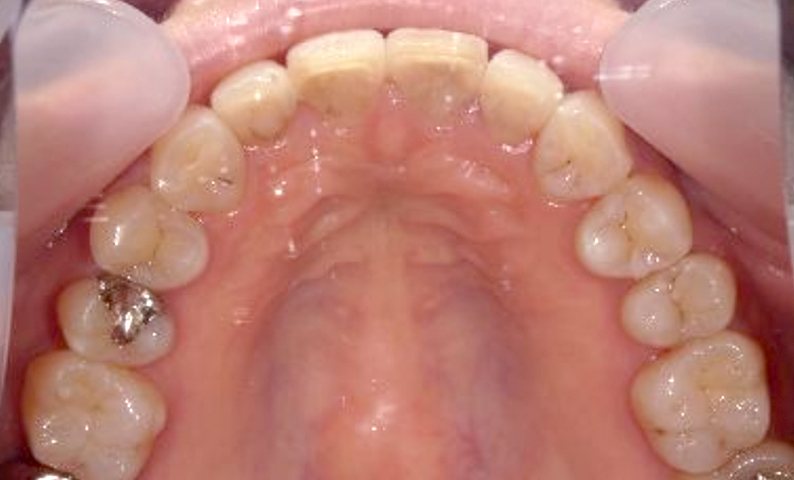

症例_003 上下顎の部分矯正

治療期間:12ヶ月金額:54万円+税男性八重歯前歯のガタガタ

| Before | After |

|---|---|

|